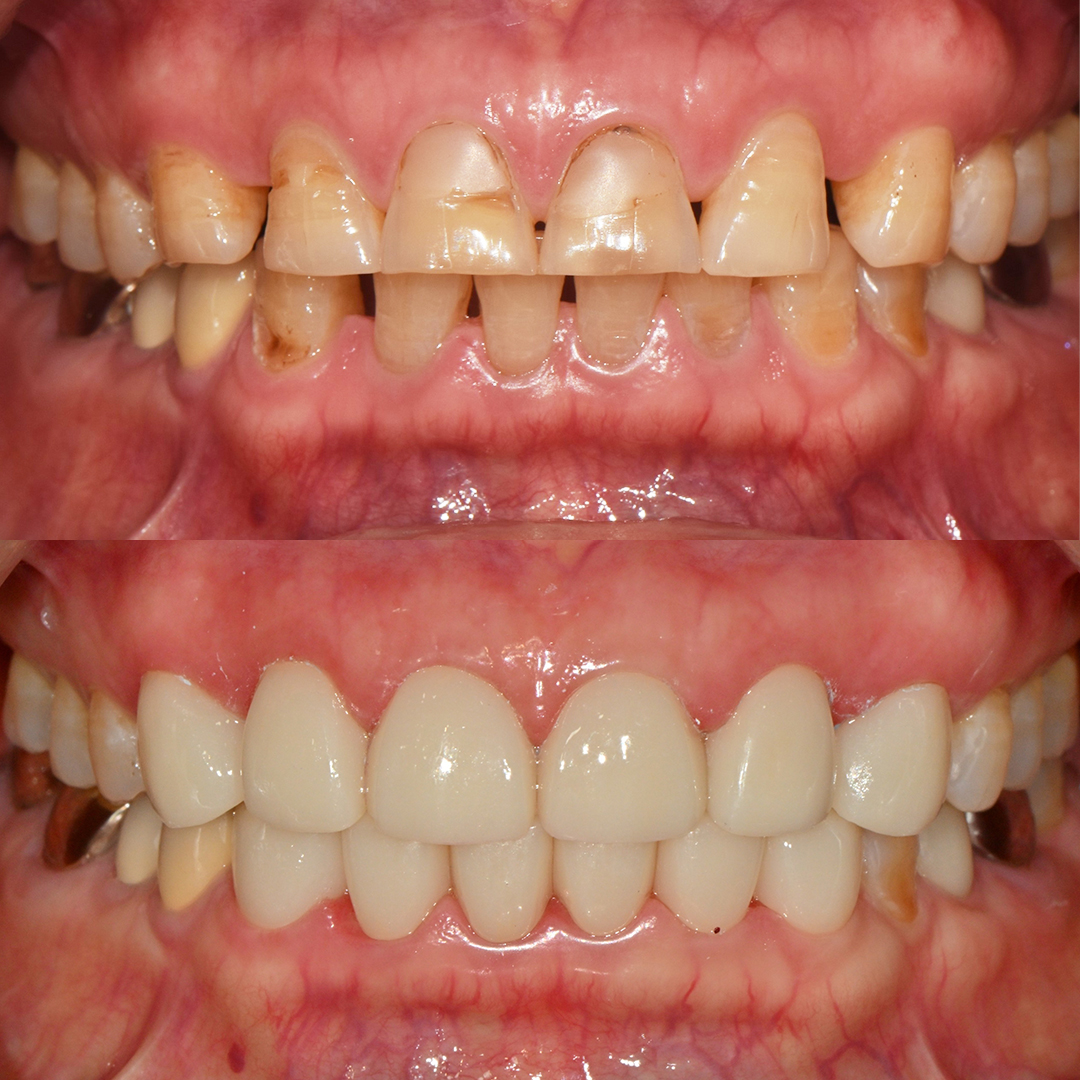

- 임플란트

- 심미보철

평균 악당 30분의 빠른 식립시간, 치료 케이스 다수 보유

전체 임플란트

상·하악 전체 치아를 대체하는 임플란트로 최소한의 식립을 통해

자연치아와 비슷한 기능을 수행할 수 있도록 합니다.